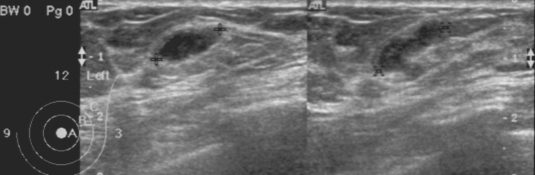

Mammography showed multiple, well-defined, isodense, lobular, and continuous cord-like structures in the upper outer quadrant of the left breast (Fig. 1). Ultrasonographic findings also showed well-defined, hypoechoic, tubular masses with folded band-like tracts and a tubule-in-tubule appearance, in the parenchymal layer of the left breast (Fig. 2). A neoplastic disease could not be ruled out, and therefore, fine needle aspiration biopsy was performed on the breast mass, which showed no evidence of neoplastic diseases. Then, breast sparganosis was suspected.

Breast sparganosis presents as soft tissue nodules, as in the present case, and is confused with neoplastic masses in radiological images (Chuen-Fung and Alagaratnam, 1991; Jeong et al., 1995). For example, its mammographic features are usually multiple, lobular, marginated, amorphic, and solid masses without calcifications, which are similar to the features of the circumscribed breast cancer or benign tumor-like fibroadenoma (Chung et al., 1995; Kim et al., 2005). Thus, a confirmatory diagnosis should be established by extracting the worm responsible or by examining surgical pathology specimens. However, as shown in the present case, mammography findings can be characteristic and highly useful for a pre-operative diagnosis of breast sparganosis.

Ultrasonographic findings may also be useful for the pre-operative diagnosis of breast or other organ sparganosis (Chung et al, 1995; Cho et al., 2000; Kim et al., 2005). In breast sparganosis, elongated, folded, band- or tunnel-like hypoechoic tubular structures in heterogenous, hyperechoic masses are characteristic (Chung et al., 1995), whereas in subcutaneous and musculoskeletal sparganosis, serpiginous, cystic, tubular tracts, with internal anechogenicity and posterior echo enhancement, are important characteristics (Cho et al., 2000). Intraluminal lesions formed by the larvae or debris and peritubular echo changes produced by chronic inflammatory reactions have been noted in a half of musculoskeletal sparganosis cases (Cho et al., 2000). However, findings of elongated, serpiginous, and tubular structures may also be obtained in other types of diseases, such as, ectatic ducts, radiation edema, superficial thrombophlebitis, and congestive heart failure (Chung et al, 1995; Kim et al., 2005). Nevertheless, such findings together with high antibody titers against sparganum, and characteristic mammography and ultrasonography findings will be very useful for a pre-operative diagnosis of sparganosis.

Fig. 1

Mammogram of the present breast sparganosis case. A: Mediolateral oblique view, B: Craniocaudal view. Welldefined, isodense, lobular, and continuous cord-like structures (arrows) were characteristically observed in the upper outer quadrant of the left breast.